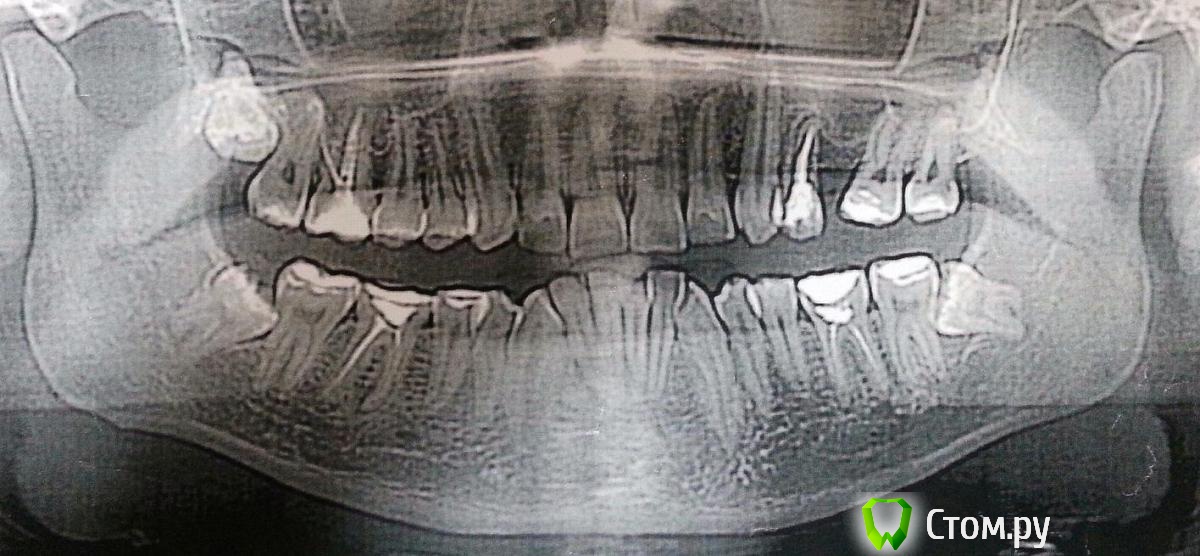

minchia Опубликовано 1 января, 2014 Автор Поделиться Опубликовано 1 января, 2014 Спасибо за ответ. Конечно я задавал данный вопрос ортодонту, она сказала что это общепринятая практика, и что я привыкну.Но я буду все же убирать эти накусочные площадки, так как невозможно жевать. Буду осторожно обращаться, чтобы не слетели брекеты. У меня к тому же массивные пломбы на этих шестерках, они депульпированы, наличие накусочных пломб может их окончательно убить.Панорамный снимок приложен. На данном снимке не отражены последние изменения - удалены три восьмерки - 18, 38 и 48. Ссылка на комментарий